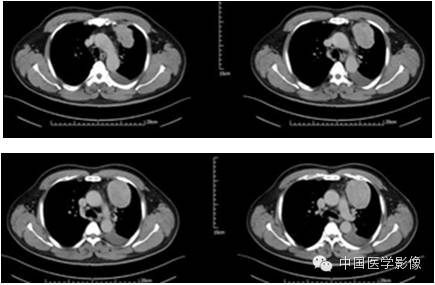

病例2【病史】

患者男,47岁。

患者因“查体发现右纵膈区占位2周”入院。患者无胸痛、胸闷,无发热、盗汗,无咳嗽、咳痰。CT示:右心膈角处新生物,考虑来自叶间裂的炎性假瘤可能性大,不除外其他肿瘤可能。

专科查体:(-)

入院诊断:右下纵膈占位:心包囊肿?炎性假瘤?

【影像资料】

平扫

动脉期

静脉期

延迟期

结果马上公布……

【病理结果】

孤立性纤维性肿瘤